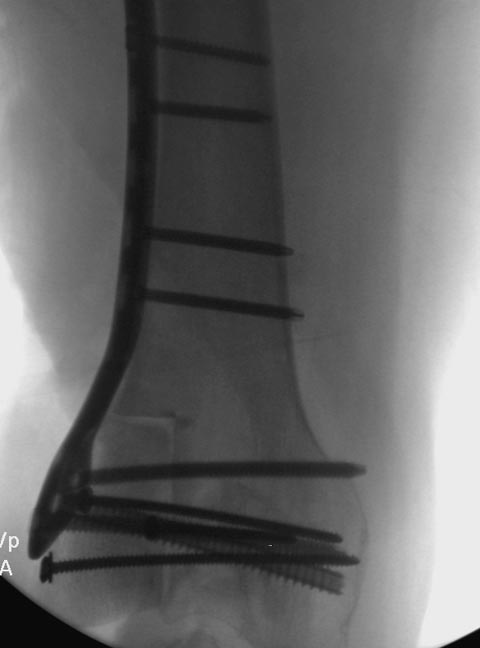

Здесь представлен посттравматический дефект латерального мыщелка и

лечение аллографтом.

Вложение не в текстовом формате было извлечено…

Имя     : Medial Tibial plateau 7.jpg

Тип     : image/jpeg

Размер  : 30290 байтов

Описание: отсутствует

Url     : http://weborto.net:8080/pipermail/ortho/attachments/20141113/94e46382/attachment-0007.jpg